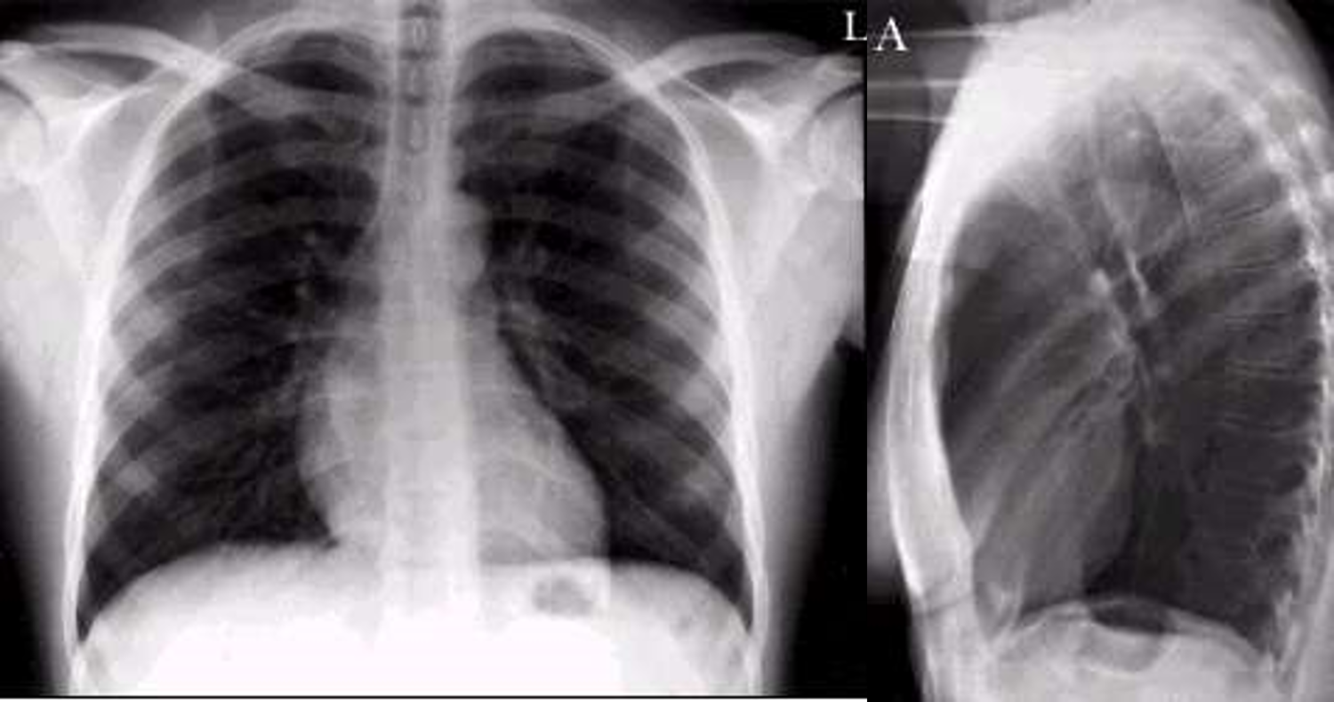

52yo female smoker presents to the clinic with 5 month history of a chronic productive cough

View: PA and lateral

DX: COPD